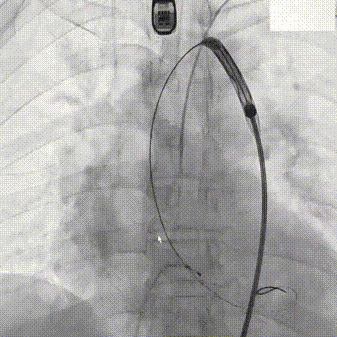

主动脉根部造影

20mm TaurusAtlas球囊

输送系统过弓

确定初始释放位

瓣膜稳定释放至工作位

TaurusOne AV23mm瓣膜瓣下3-4mm 工作位造影

瓣膜完全释放

瓣膜位置理想